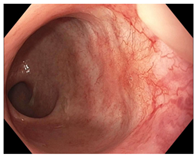

| Endoscopy | Flat white scar Telangiectasia Absence of ulcers and mucosal nodularity | Small mucosal nodules/minor mucosal irregularities Superficial ulceration Mild, persistent erythema of the scar | Visible tumor |

| Small mucosal nodules, minor mucosal irregularities | ![]() | ![]() | ![]() |

| Superficial ulceration | ![]() | ![]() | ![]() |